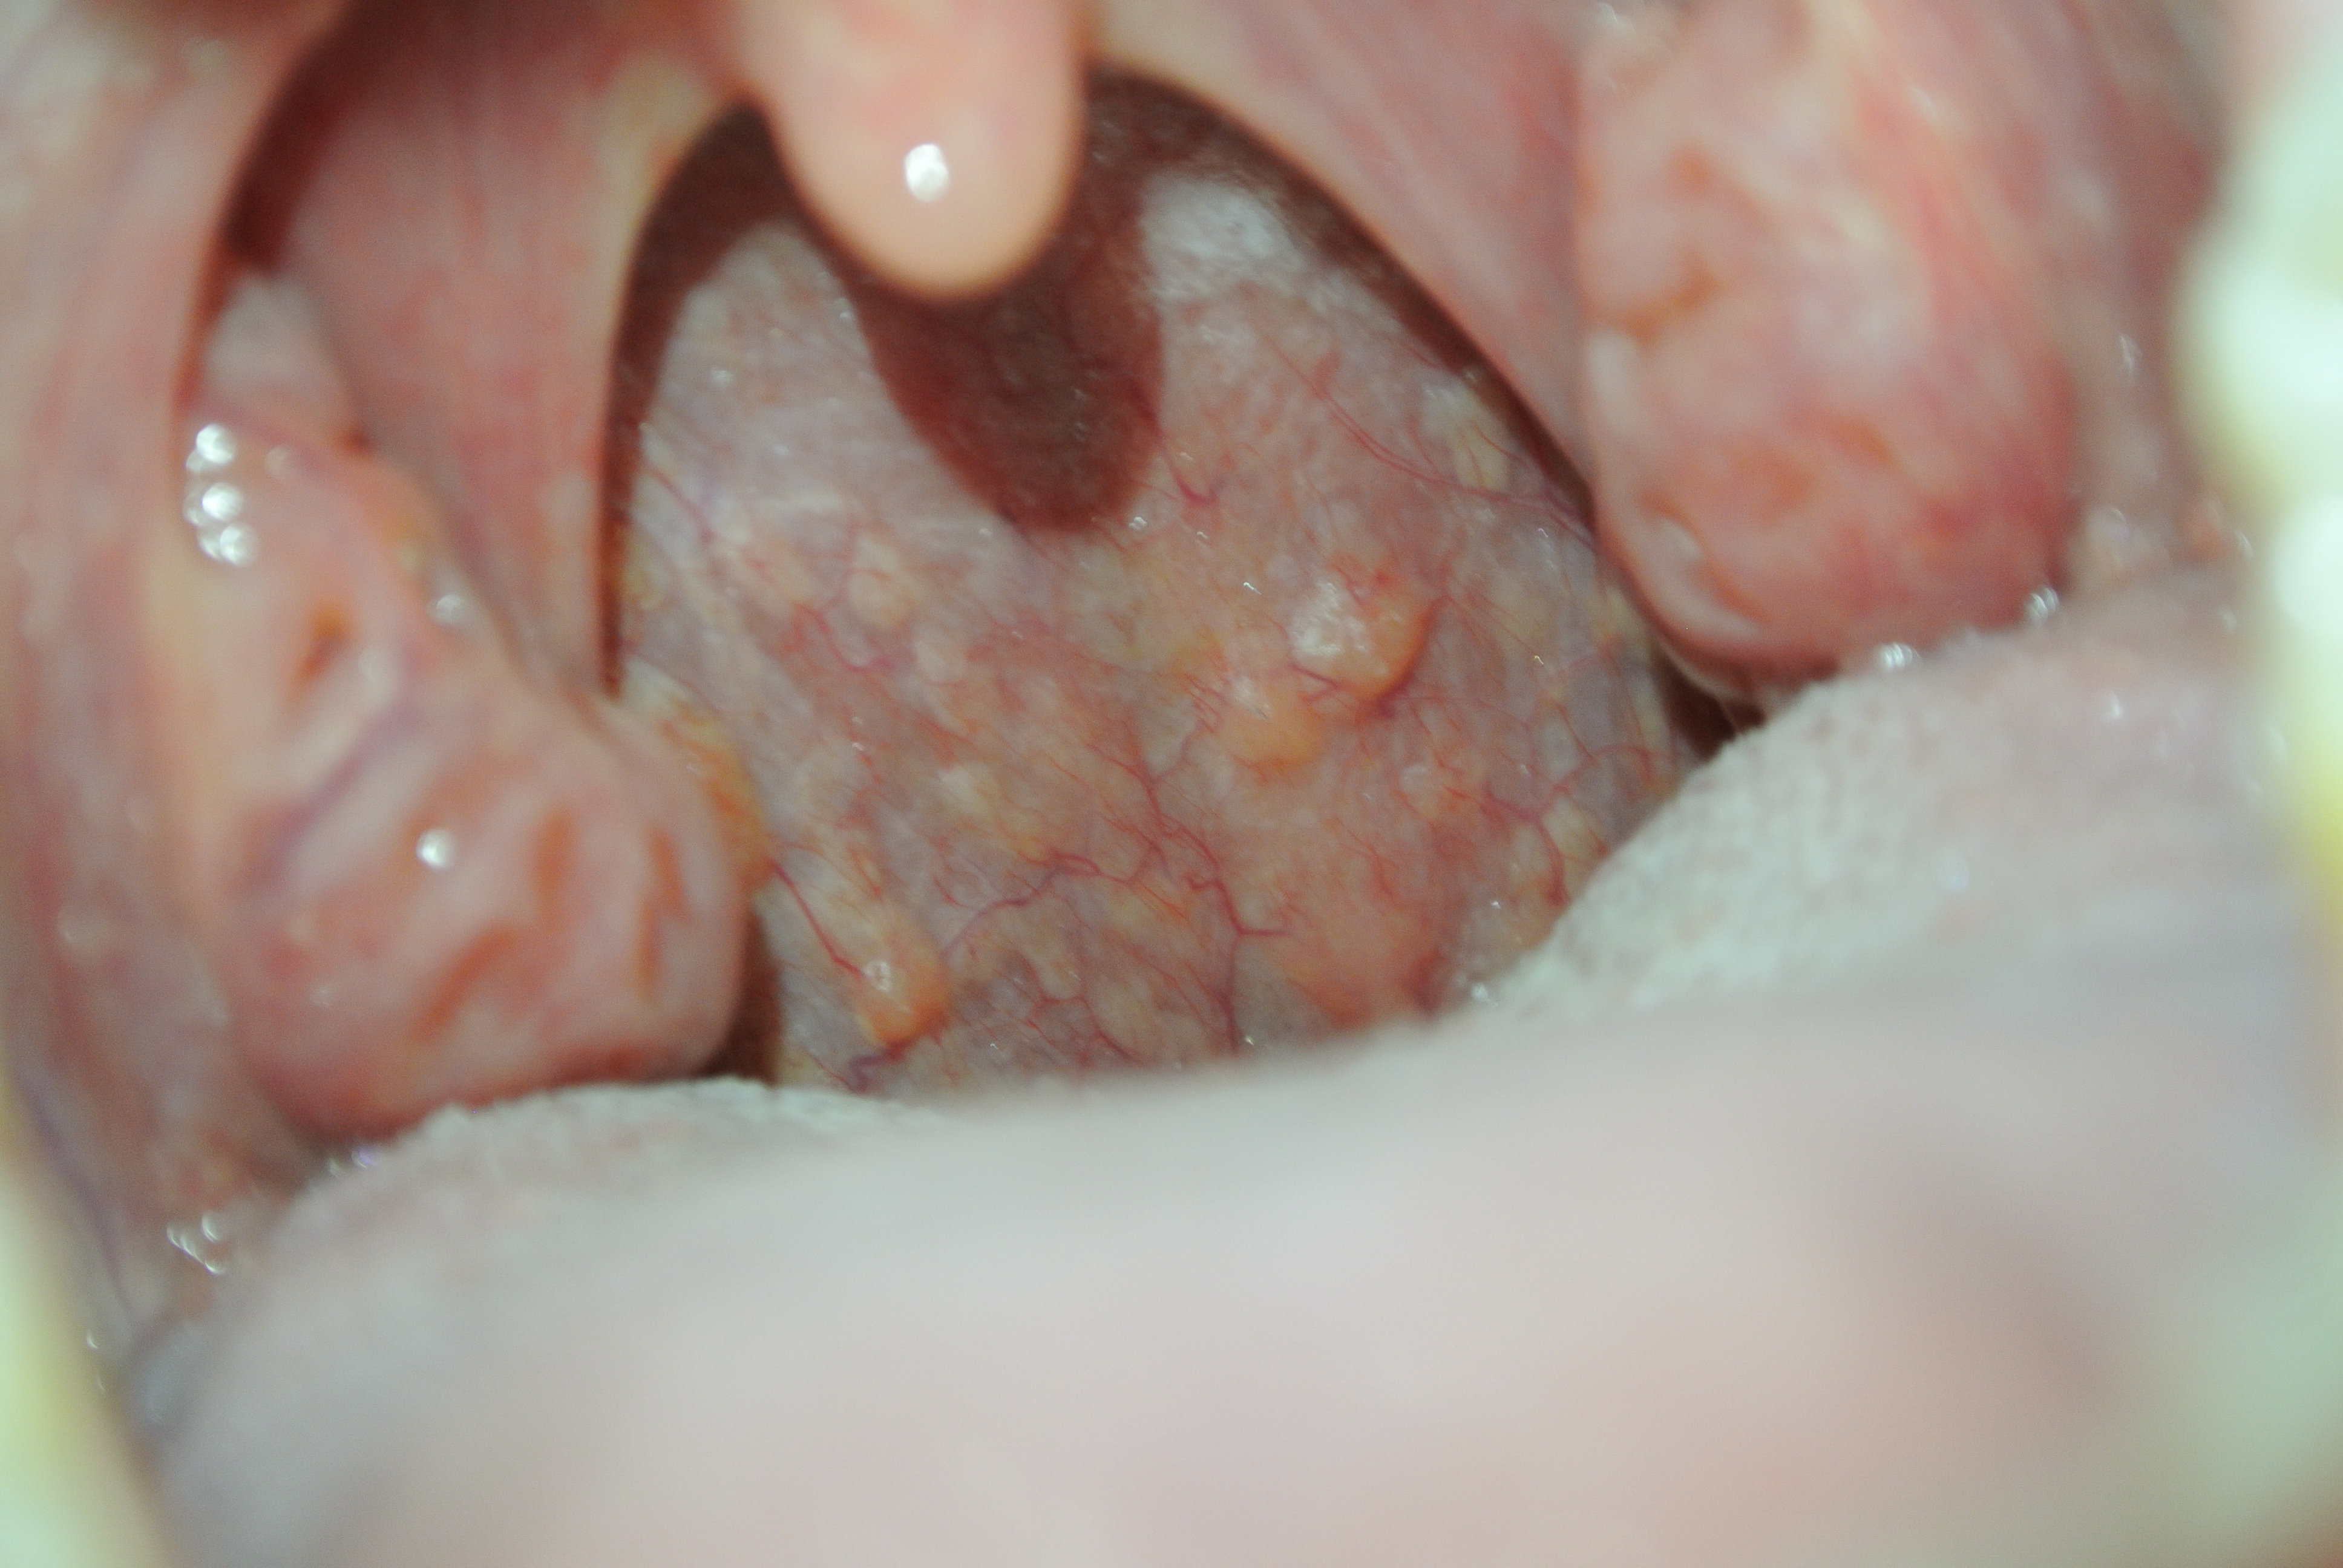

Questo è successo ormai due mesi fa, ora è tutto cambiato, ho un fastidio continuo alla gola che peggiora prima di andare a letto, mi sembra di avere quasi un impedimento, come se fosse gonfia la gola a livello della laringe. Però respiro bene e deglutisco bene. Ultimamente ho notato un'altra cosa, delle strane bollicine a livello di parete posteriore dell'orofaringe (allego foto).

Allegato:

DSC_1324.JPG

[ 4.85 MiB | Osservato 1738 volte ]